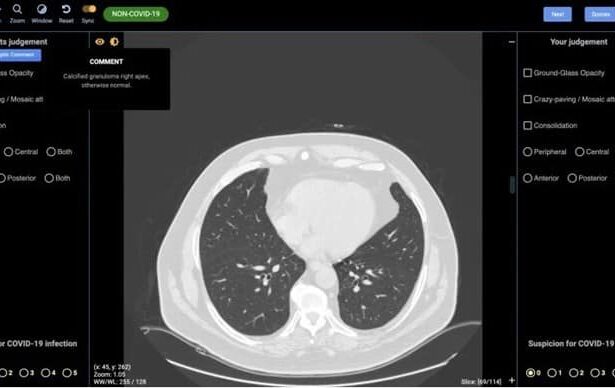

Sau hơn 1 năm lây lan, virus SARS-CoV-2 gây nên đại dịch trăm năm có một trên thế giới (Ảnh minh họa: Getty)